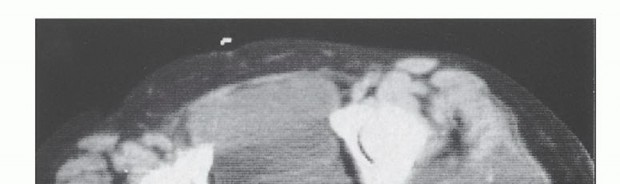

صورة: تُظهر الأشعة المقطعية ساركوما غضروفية كبيرة خارج العظم في الأرداف (Tu) مع بقاء حافة رقيقة من العضلة الألوية الكبرى (G). هناك امتداد مبكر داخل الحوض عبر الثلمة الوركية (السهم). هذه حالة نموذجية تستدعي هذا الإجراء.